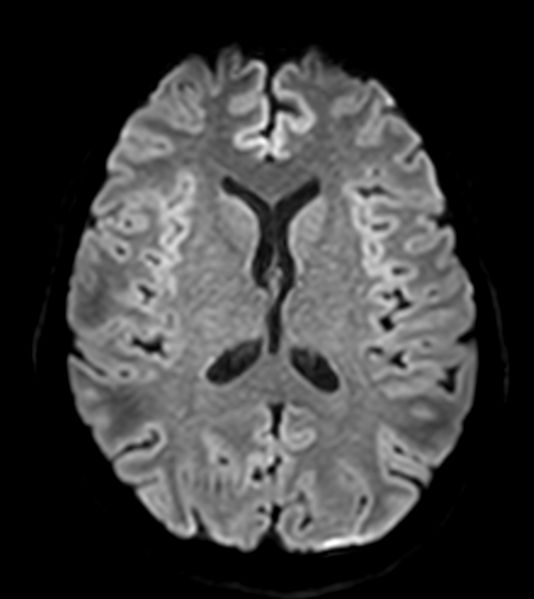

Axial DWI b1000

-

Axial DWI b1000 (ADC)